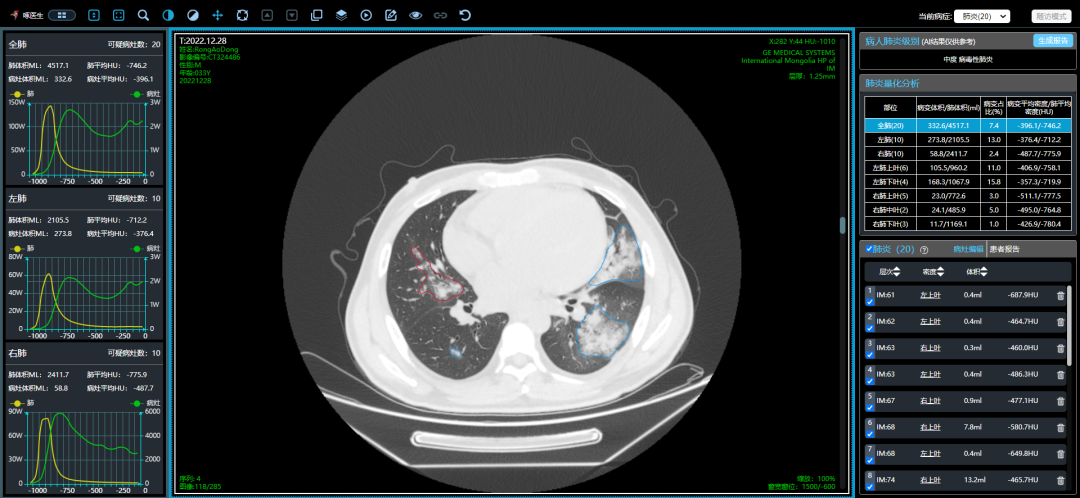

從這3個確診新冠肺炎呈“白肺”病例來看,“白肺”多見于老人、兒童以及帶有基礎(chǔ)病的新冠患者,病灶可發(fā)生在肺內(nèi)任何肺葉,病灶形態(tài)特點也是多樣化,符合病毒性肺炎的影像表現(xiàn)。從影像學(xué)角度出發(fā)重點在于快速評估病情,提升人工讀片的客觀性。 “啄醫(yī)生閱片機器人??新冠肺炎CT影像輔助分診與評估系統(tǒng)”可以準確地識別新冠肺炎的典型影像表現(xiàn)如雙肺外周胸膜下多發(fā)的磨玻璃影、小葉間隔增厚或合并鋪路石征等,對于部分患者由于影像表現(xiàn)早于臨床癥狀,更具有早期發(fā)現(xiàn)、早期診斷的優(yōu)勢。